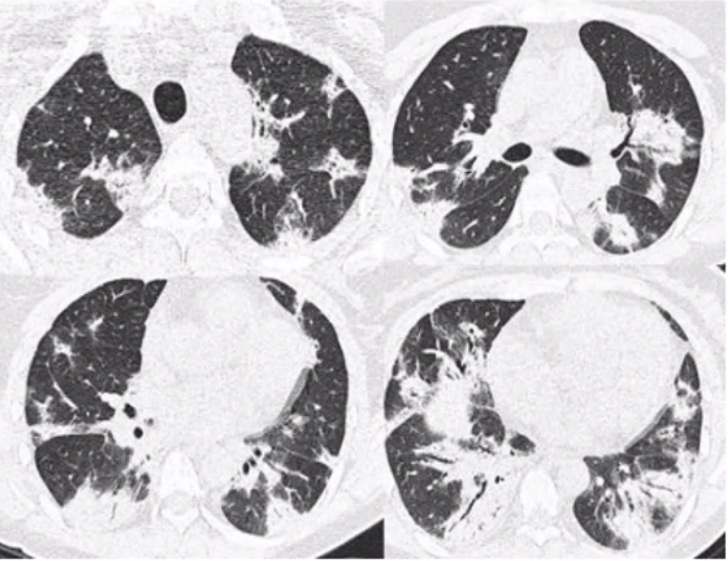

HRCT in COP

consolidation with GG/small nodules Basal/subpleural/peribronchial, can migrate spontaneously solitary mass (less common) septal thickening *reverse halo/Atoll sign, highly specific*

32